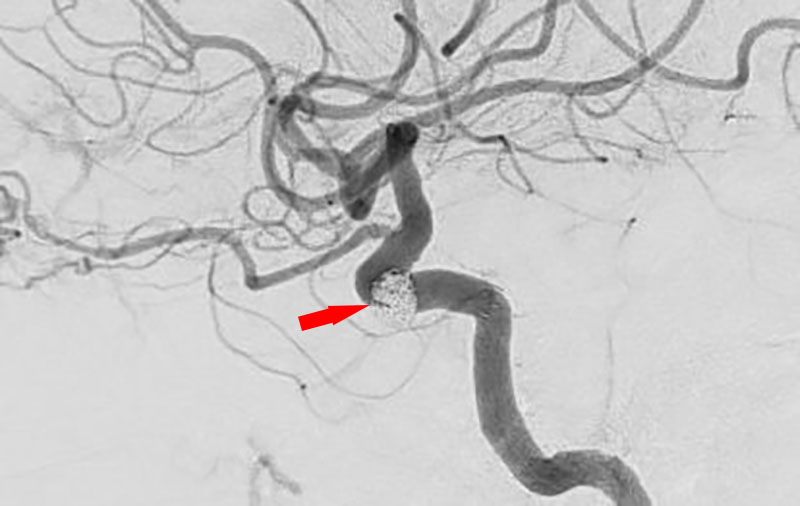

No.1617 手術中